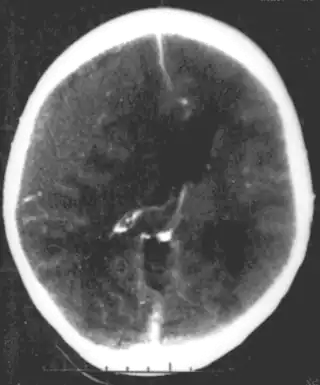

![]() Hematoma Epidural no traumático en una mujer joven. El área gris en la parte superior externa es el hematoma, que causa desviación de la línea media y compresión ventricular. | ||

Un hematoma epidural es una acumulación de sangre que ocurre entre la duramadre (que es la capa que rodea al sistema nervioso central por fuera y al cráneo por dentro) y la superficie interna del cráneo.[1] Debido a que la duramadre también recubre a la médula espinal, un sangrado epidural puede también presentarse en la columna. En la mayoría de los casos se deben a traumas físicos y produce un aumento en la presión intracraneal e incluso puede verse reflejado en desviación de la línea media de las estructuras cerebrales, y puede llegar a ser mortal, por lo tanto, un hematoma epidural es una emergencia médica.[2] En la imagen por tomografía suele observarse una imagen biconvexa, a diferencia del hematoma subdural que muestra una imagen cóncava en su cara interna.